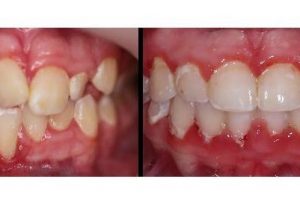

Posted by Lenk Orthodontics on Thursday, January 28, 2021 Lenk Orthodontics isn’t just about teeth: OUR FOCUS IS THE SMILE, BITE, AND OVERALL ESTHETICS…. LOOK AT THE DIFFERENECES IN THIS …

Another great example of why early detection is important!!! Early detection prevented damage to roots, prevented the extraction of teeth, and prevented the need for surgical intervention!! The lower …